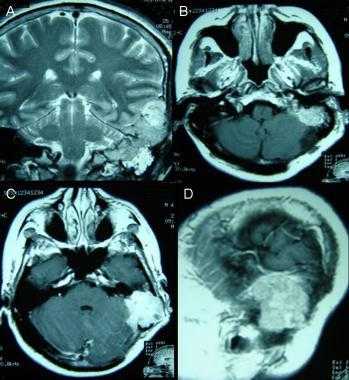

(Слева) КТ в костном окне, аксиальная проекция. Характерные инфильтративно-склеротические костные изменения в области основания черепа и яремного отверстия. Обратите внимание, что внутричерепная часть опухоли частично кальцифицирована.

(Справа) МРТ Т1ВИ FS с КУ, аксиальная проекция. Менингиома яремного отверстия распространяется вниз, в сонное пространство. Обратите внимание, что сонная артерия расположена спереди от опухоли. Подобные опухоли происходят из клеток арахноидального эндотелия. Увеличиваясь в размерах, менингиома начинает спускаться в сонное пространство. (Слева) МРТ Т1ВИ FS с КУ, аксиальная проекция. Крупная, накаливающая контраст опухоль правого сонного пространства, смещающая сонную артерию кпереди. Обратите внимание, что участки выпадения сигнала отсутствуют. Этот признак помогает дифференцировать менингиому от более распространенной опухоли-параганглиомы.

(Справа) МРТ Т1ВИ FS с КУ, коронарная проекция, тот же пациент. Крупная менингиома сонного пространства, исходящая из яремного отверстия. Обратите внимание, что в полости черепа имеется «хвост» из твердой мозговой оболочки -достаточно частая находка у пациентов, у которых менингиома основания черепа распространяется интракраниально.

(Справа) МРТ Т1ВИ FS с КУ, аксиальная проекция. Менингиома яремного отверстия распространяется вниз, в сонное пространство. Обратите внимание, что сонная артерия расположена спереди от опухоли. Подобные опухоли происходят из клеток арахноидального эндотелия. Увеличиваясь в размерах, менингиома начинает спускаться в сонное пространство.

(Слева) МРТ Т1ВИ FS с КУ, аксиальная проекция. Крупная, накаливающая контраст опухоль правого сонного пространства, смещающая сонную артерию кпереди. Обратите внимание, что участки выпадения сигнала отсутствуют. Этот признак помогает дифференцировать менингиому от более распространенной опухоли-параганглиомы.